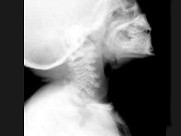

- 单项选择题女,3岁, 身高不增,智力正常, 结合图像,最可能的诊断是 ( )

C、黏多糖贮积症Ⅳ型